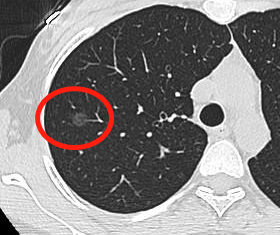

毛玻璃结节-中危

恶性几率高于上图